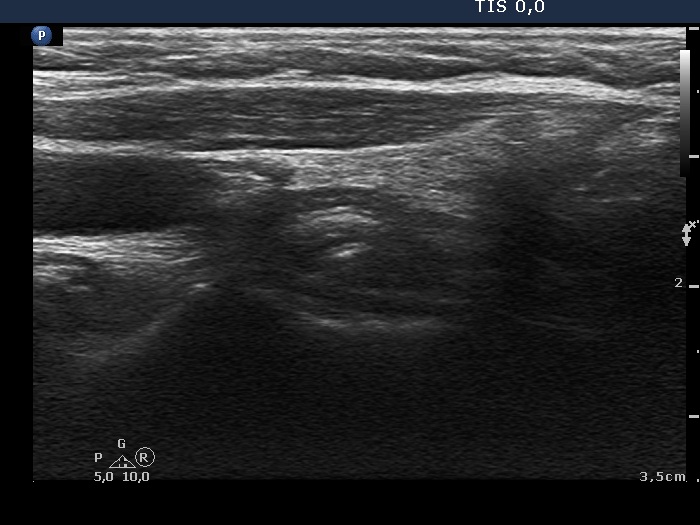

The operated thyroid - case 775 |

Clinical data: A 55-year-old woman was referred for follow-up examination. She underwent total thyroidectomy because of toxic multinodular goiter 7 years ago. She had no complaints.

Ultrasonography: There was no parenchyma according to the thyroid lobes.